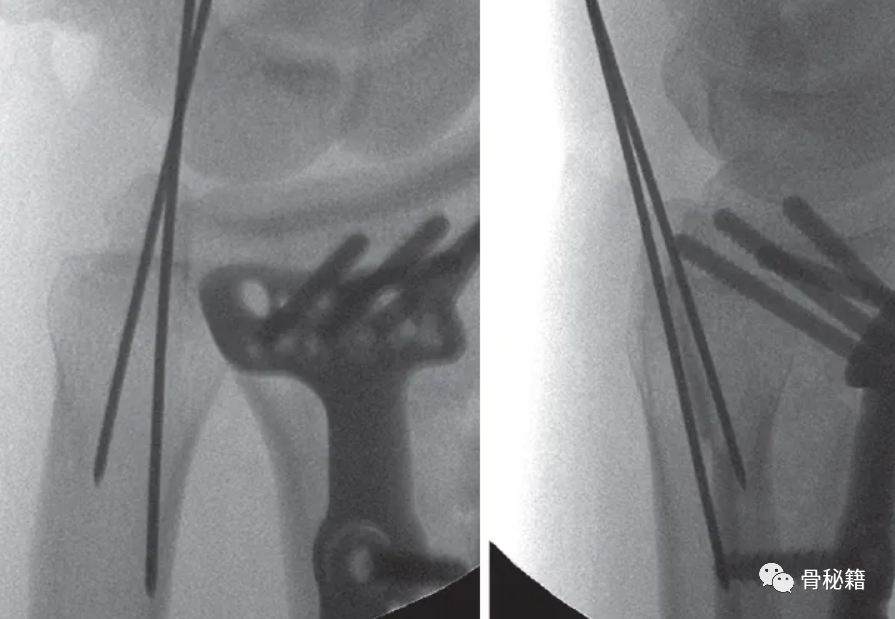

采用茎突入路进行手术复位与固定,拧入空心螺钉

固定后 术中用探钩检查TFCC稳定性,发现固定后稳定性较好

2、中心凹入路:用于 TFC 脱离和头部骨折

通过一个 1.5 到 2 厘米的切口,从茎突底部的背侧近端到掌侧远端切开,注意不要损伤尺神经,保持尽量旋后的状态,也可通过该入路重建TFCC